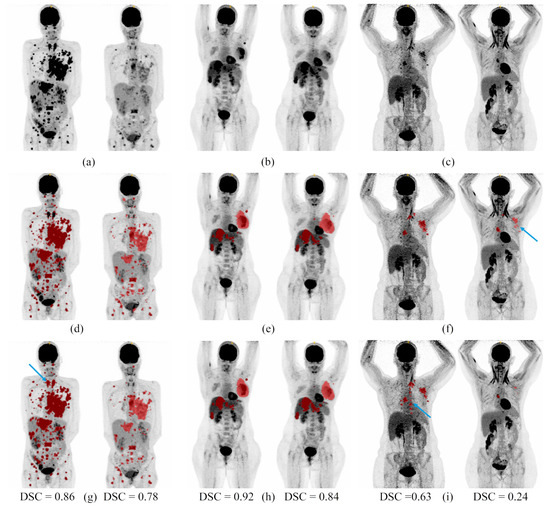

- Development of a deep learning network to segment breast cancer metastatic lesions on baseline acquisitions with whole-body PET/CT images as input. Our network achieved a mean dice score of 0.66.

- Development of a deep learning network to segment breast cancer metastatic lesions on follow-up acquisitions with whole-body PET/CT images as input. The difference of this network compared to the previous one lies in the use of baseline PET images and lesion segmentations as complementary inputs to the follow-up PET/CT images. This allows a better segmentation of the follow-up lesions that often present a lower contrast due to treatment response. Our network achieved a mean dice score of 0.58.